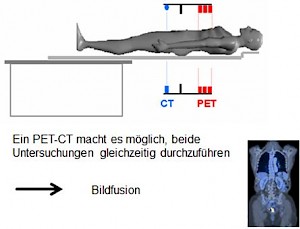

Die PET/CT ist eine Kombination aus zwei unterschiedlichen bildgebenden Untersuchungsverfahren:

- PET = Positronen-Emissions-Tomographie

- CT = Computertomographie

PET ist ein nuklearmedizinisches Untersuchungsverfahren, CT ein radiologisches Untersuchungsverfahren. Es wird folgendes bildlich dargestellt:

- PET = Stoffwechselvorgänge

- CT = anatomische Strukturen

- Zunächst wird ein CT-Topogramm des Patienten angefertigt anhand dessen die anatomischen Aufnahmebereiche der CT und der PET festgelegt werden.

- Dann folgt eine native CT-Untersuchung in Low-Dose Technik des gesamten Untersuchungsbereiches, meist von der Schädelbasis bis zur Mitte beider Oberschenkel.

- Dann erfolgt die PET-Untersuchung. Diese ist meist in 8 bis 9 Bettpositionen unterteilt.

- Mit dem Low-Dose-CT wird eine Schwächungskorrektur der PET-Daten vorgenommen, um Schwächungseffekte im aufgenommenen Körper herauszurechnen.

- Bei entsprechender klinischer Indikation schließt sich eine Normaldosis-CT mit KM einer ausgewählten Körperregion, zum Beispiel des Thoraxes an.

- Zuletzt werden die schwächungskorrigierten PET-Daten mit den CT-Daten fusioniert und ergeben den PET-CT-Datensatz.